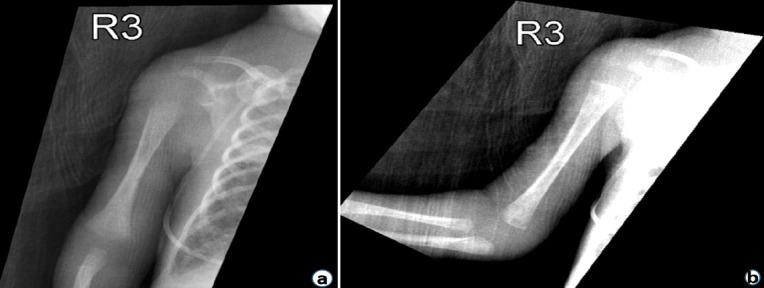

We present a case of a pre-mature neonate with diffuse discoloration, paralysis, and loss of palpable pulses of the right upper extremity after a failed PICC insertion. The clinical features led to a diagnosis of compartment syndrome. Interventions were not carried out due to the pre-maturity and instability of the patient. The patient passed away at 38 days of age due to refractory hypotension and patent ductus arteriosus.